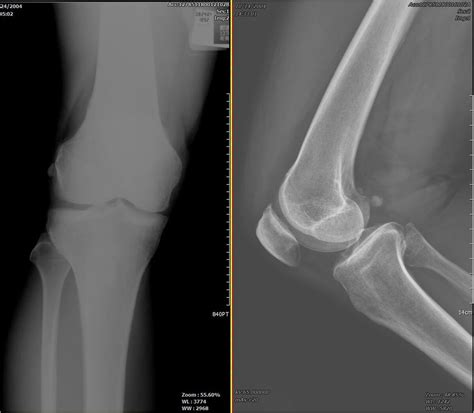

Anatomy of the Knee Joint

The knee is formally classified as a synovial hinge joint, but its functionality is far more nuanced. To understand how it works, we must first look at the four primary structural components that make up the bones of the knee. These structures do not act in isolation; rather, they form the foundation upon which muscles, ligaments, and tendons attach to create motion.

• The Femur (Thigh Bone): This is the largest and strongest bone in the body. The distal end of the femur features two rounded projections called condyles, which act as the "rockers" that glide across the top of the tibia.

• The Tibia (Shin Bone): Serving as the primary weight-bearing bone of the lower leg, the top of the tibia (the tibial plateau) provides a flat surface for the femur to rest upon.

• The Patella (Kneecap): This triangular sesamoid bone is embedded within the quadriceps tendon. Its primary function is to increase the leverage of the thigh muscles, making it easier to straighten the leg.

• The Fibula (Calf Bone): While it is not a direct participant in the hinge motion of the knee joint, the fibula is connected to the tibia and serves as an important anchor point for several crucial ligaments and muscles that stabilize the knee.

The way the bones of the knee interact determines the range of motion of the lower limb. The femur and tibia are not perfectly flat; their surfaces are slightly curved. This curvature allows for a combination of gliding, rolling, and even slight rotation. Because these bones are hard, they rely on articular cartilage to prevent friction during movement. This smooth, white tissue covers the ends of the bones, acting as a shock absorber that protects the skeletal structure from the stresses of daily activity.

When the knee bends, the patella slides through a specific groove on the femur known as the trochlear groove. If this tracking is slightly off, it can lead to pain or wear on the cartilage. Maintaining balanced leg strength is one of the best ways to ensure these bones continue to interact correctly throughout your life.